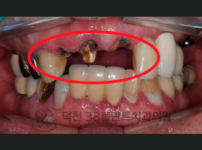

치료전후